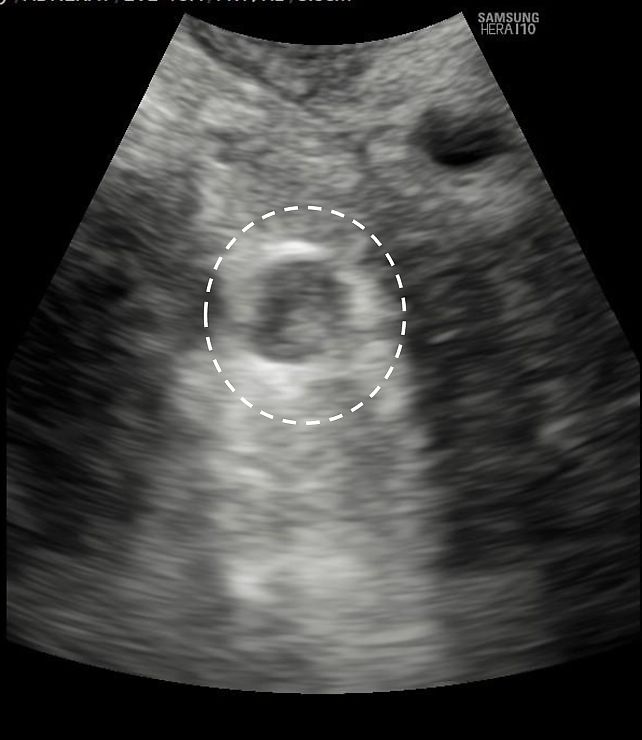

Hyperechogenic ring, raising suspicion of metastasis, visualized using a convex probe.

15

Pelvic (external iliac) lymph node, visualized using a convex probe, showing cystic area (dashed circle).